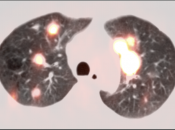

Metastatic Disease: Metastatic RCCA lesions are usually more FDG avid than the primary lesion (nearly all demonstrate metabolic activity greater than liver uptake).

- Hematogenous spread, often to lungs, bone, liver, and brain.

False Negatives:

- Low-grade lesions

- Lesion masked by normal urine activity

- Primary lesions < 8.0 mm

- Nodes or metastatic lesions < 8.0 mm